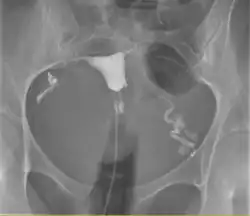

Hystérosalpingographie. Notez le cathéter entrant en bas de l'écran, et le produit de contraste sombre remplissant la cavité utérine (petit triangle au centre) et délimitant les trompes de Fallope (structures sinueuses à gauche et à droite).

L'hystérosalpingographie est un examen de radiologie qui permet de visualiser l'utérus ainsi que son col et les trompes de Fallope.